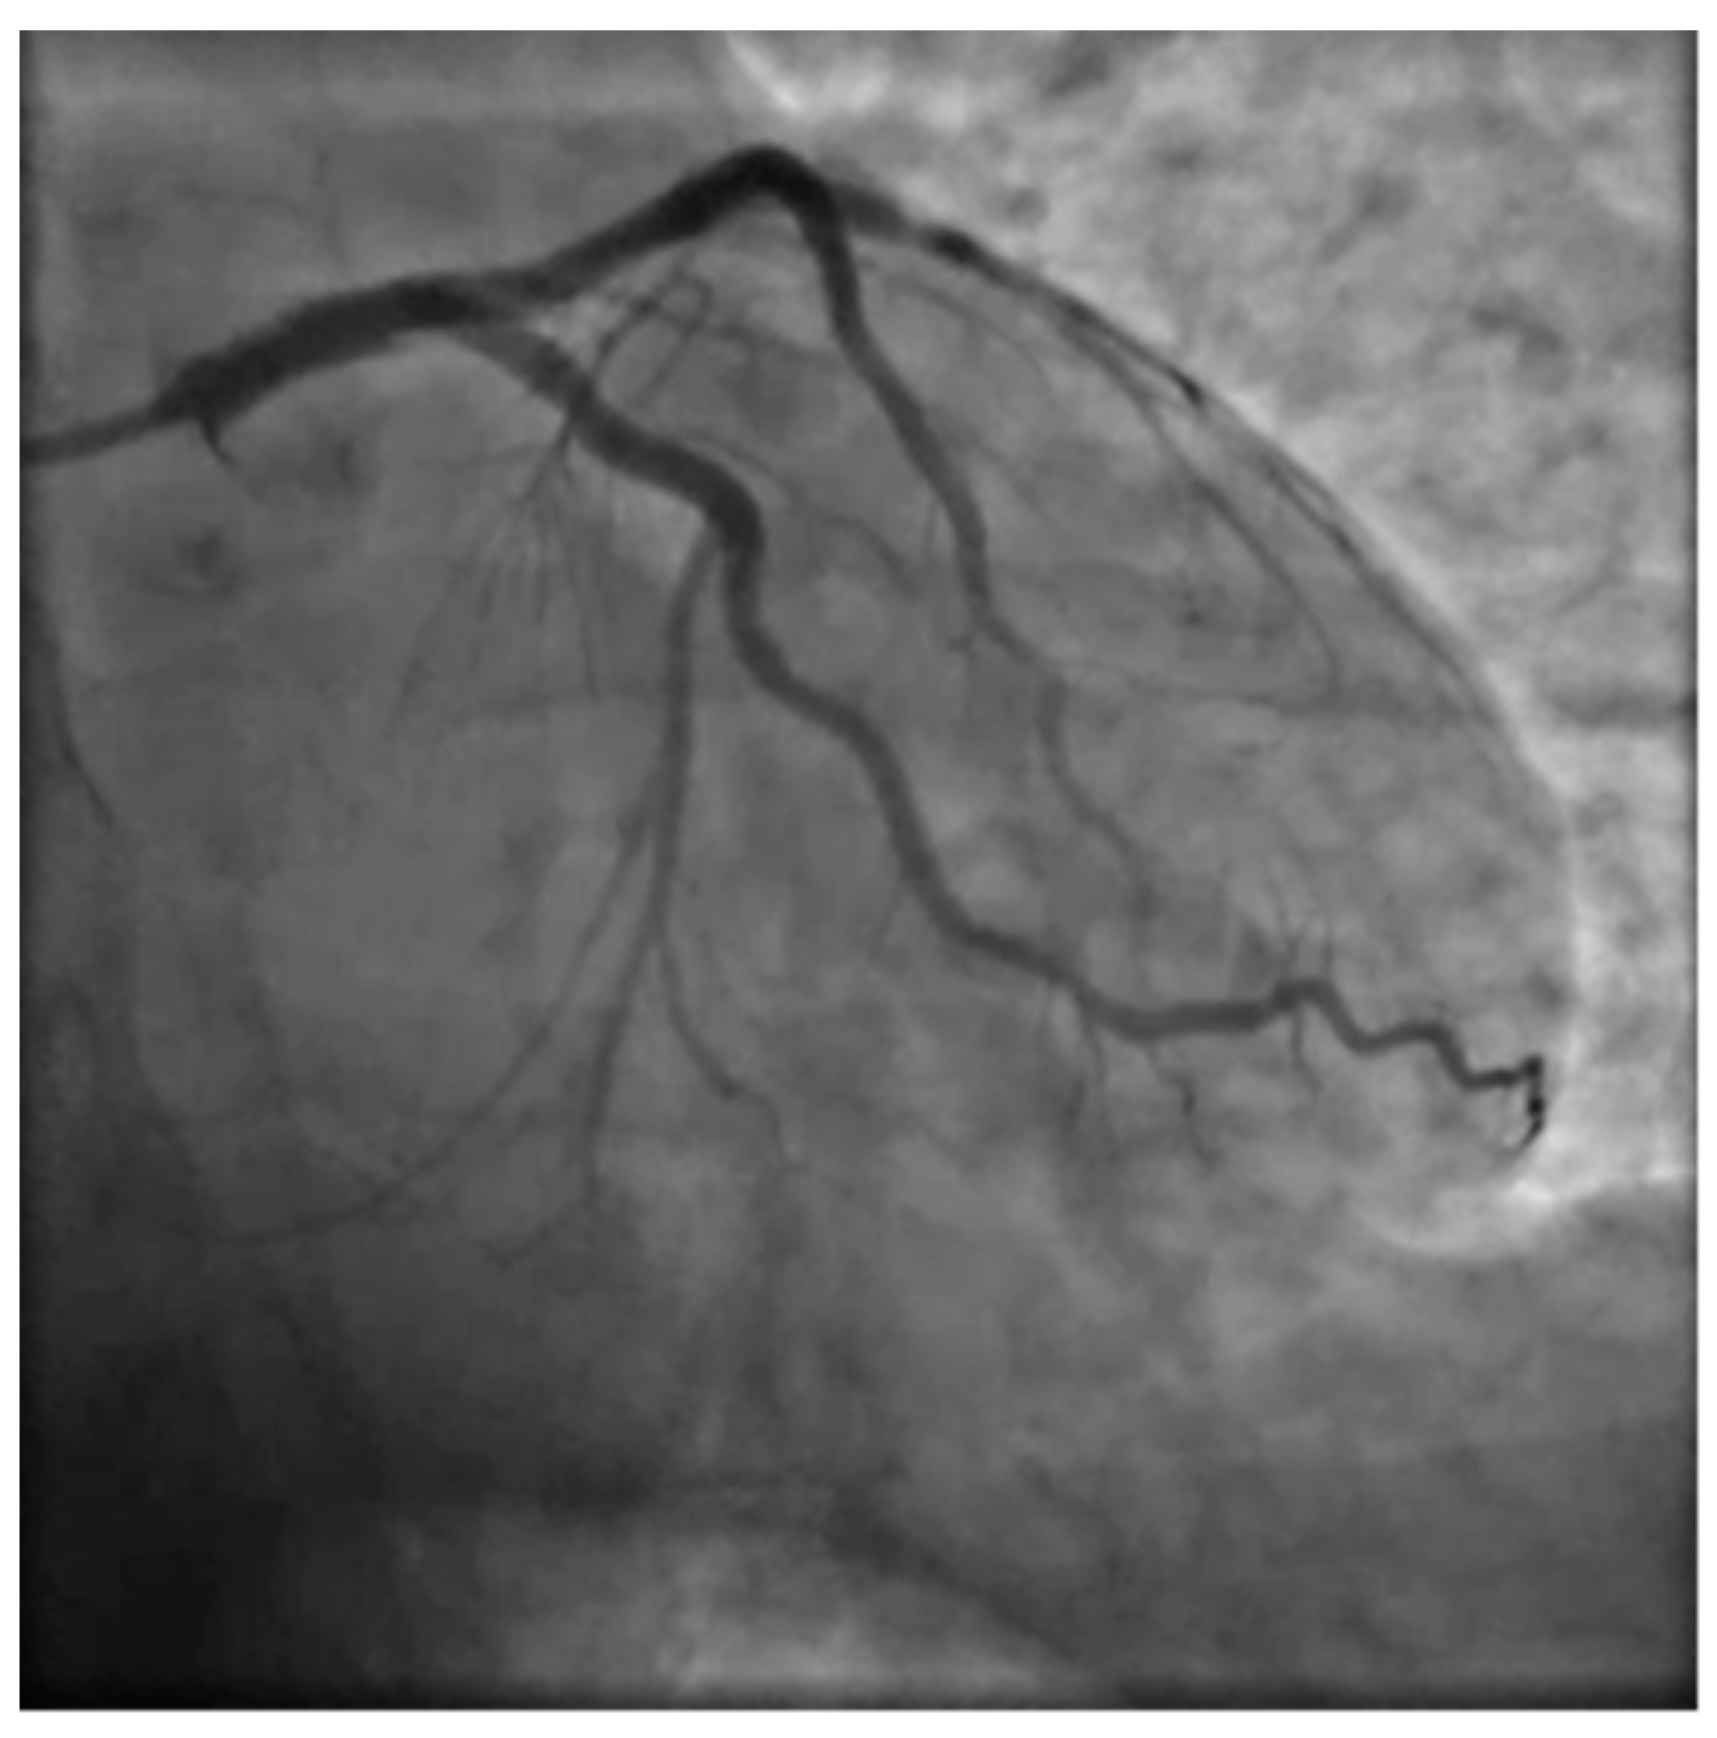

Due to the unusual setting involving a 36 weeks pregnant woman several other specialists were involved in the care process setting up an emergency pregnancy heart team involving cardiologists, gynecologists, anesthesiologists, pediatricians and the radiology specialist. Due to the unstable and acute condition of the woman a decision was quickly made to proceed with an emergency coronary angiography and PCI. A rapid response gynecology team followed the procedure ready to intervene promptly in case of maternal deterioration with unresponsive cardiac arrest. A 6F left radial access was obtained, aiming to be as coaxial as possible, and the left coronary artery angiogram was obtained with a standard 6F JL 3.5 catheter showing LM dissection involving the ostial LAD which showed complete occlusion with TIMI 0 flow.

Percutaneous coronary intervention was therefore considered appropriate and a purposely undersized EBU 3.0 6F was selected. A safety wire, Runthrough floppy, was immediately placed on the patent left circumflex artery whilst after failing wiring on the left anterior descending with a Balance Middleweight wire a Sion wire was advanced up to the apical LAD. An IVUS run confirmed distal true lumen wire position showing a short subintimal track without compromise of any major side branch. (Figure 4, Figure 5, Figure 6 and Figure 7)

Figure 4. Basal PA caudal projection.

Figure 5. Intimal tear in the left main with hematoma.